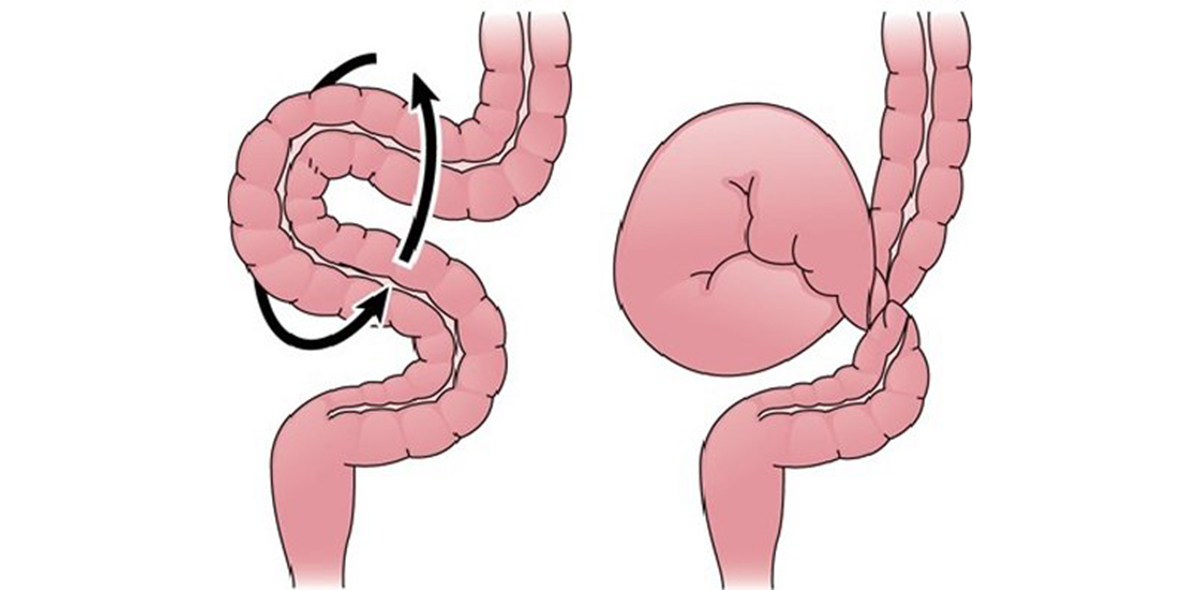

Иллюстрации и информация о симптомах острого кишечного непроходимости